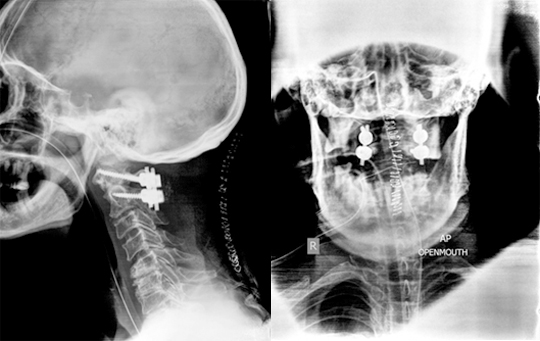

There are numerous disorders present at birth that affect the Craniovertebral Junction. These disorders may occur in isolation or be part of a generalised anomaly like Achondroplasia, Down Syndrome, Mucopolysaccharoidosis, Osteogenesis-Imperfecta, etc. Craniovertebral junction disorders may also occur later in life. They can result from motor vehicle accident, fall from a height, and certain disorders like Rheumatoid arthritis, Paget’sDisease, Ankylosing spondylitis etc. Various imaging methods like MRI, CT Scan, X rays are used for diagnosis.

Main goal of treatment is to maintain/provide spinal stability and to prevent neurological compression or trauma. Treatment depends on the exact nature of the disorder, duration of symptoms, age of the patient, degree of nerve compression, quality of bones and comorbidities, if any. Conservative management (cervical collars/braces/traction) is preferred in patients having mild symptoms without any evidence of compression of nerves and/or spinal instability. Surgery is reserved for patients with spinal instability and/or neurological symptoms.